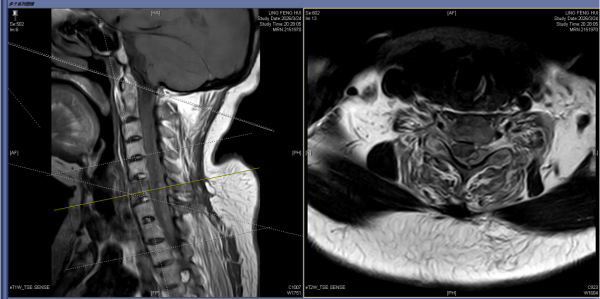

急诊入院核磁共振影像结果

62岁的张阿姨患强直性脊柱炎30余年,3月24日,她不慎摔倒后颈部着地,当即出现四肢麻木、乏力、活动受限等症状,被紧急送往长沙市中心医院急诊科救治,诊断为强直性脊柱炎、C6椎体骨折并C5/6颈椎脱位、颈、胸椎硬膜外血肿,病情危重。

颈脊髓损伤的救治黄金时间为损伤后6—8小时。患者转入脊柱外科二区后,科主任曾浩博士团队立即开启紧急救治通道,经过2天的脱水、激素冲击等对症支持治疗后,张阿姨神经功能有所改善,但危机并未解除。张阿姨长达30余年的强直性脊柱炎导致其颈椎严重僵硬前屈,下颌距胸骨上端仅2-3cm。此次摔倒造成其第5、6节段C6三柱骨折并脱位,颈胸段广泛硬膜外血肿,手术势在必行